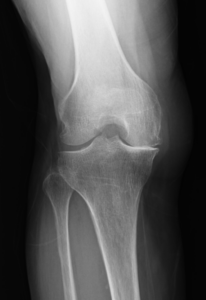

人工膝関節全置換術(TKA)

O脚やX脚が高度に進行し、関節の変形が著しく、高度の痛みを生じている方には、人工関節全置換術を行います。術前に作成した専用のガイドを用いて、脚の軸を正しく矯正しながら骨を切り、関節表面を人工関節(大腿骨・脛骨の金属パーツ+間にプラスチックパーツ)に置換します。

滑らかな動きが回復し、変形した膝がまっすぐになります。術後は翌日から荷重をかけて歩行訓練を実施します。深くしゃがむ、和式トイレを使用するといった動作が難しくなる場合があります。激しい運動は人工関節の破損につながる可能性があるため控えていただく必要がありますが、ウォーキングや水泳、テニスのダブルスなどは可能です。

本邦では年間10万人以上に行われている標準的な手術であり、その成績は安定しています。手術を受けられる方の平均年齢は70台後半であり、ご高齢の方でも受けていただける手術です。

人工膝関節単顆置換術(UKA)

膝の内側の変形に限られ、O脚変形の程度が軽度な方には、人工膝関節単顆置換術(UKA)が適応となることがあります。これは、膝関節の内側部だけを金属置換する術式で、全置換術と比べると負担も少ないため回復も早く、術後の動きはより自然に近く保たれ、生活の質も高く維持しやすくなります。

この術式を行うには、前十字靱帯や内側側副靱帯の機能がしっかり保たれていること、外側の変形が無いことが条件です。高度骨粗鬆症患者では全置換術の方が安定した成績を得ることも報告されており、術前には適応となるかの評価を要します。